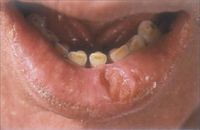

4.坏疽 gangrene指局部组织坏死合并腐败菌感染;按血液流通情况分湿性坏疽(Wet gangrene)、干性坏疽(Dry gangrene)、气性坏疽(Gas gangrene);